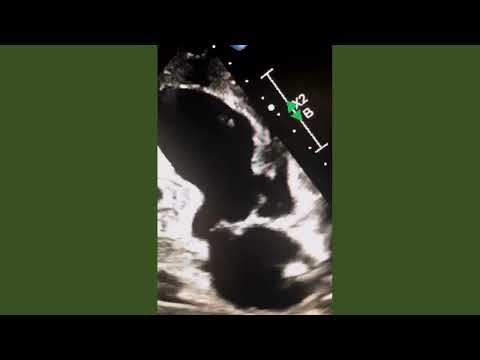

A new case on Los Angeles Echo Society YouTube Channel

Post-infarct VSD with several smaller defects with the surrounding muscu... youtu.be/vUQJHgvWGKM via @YouTube